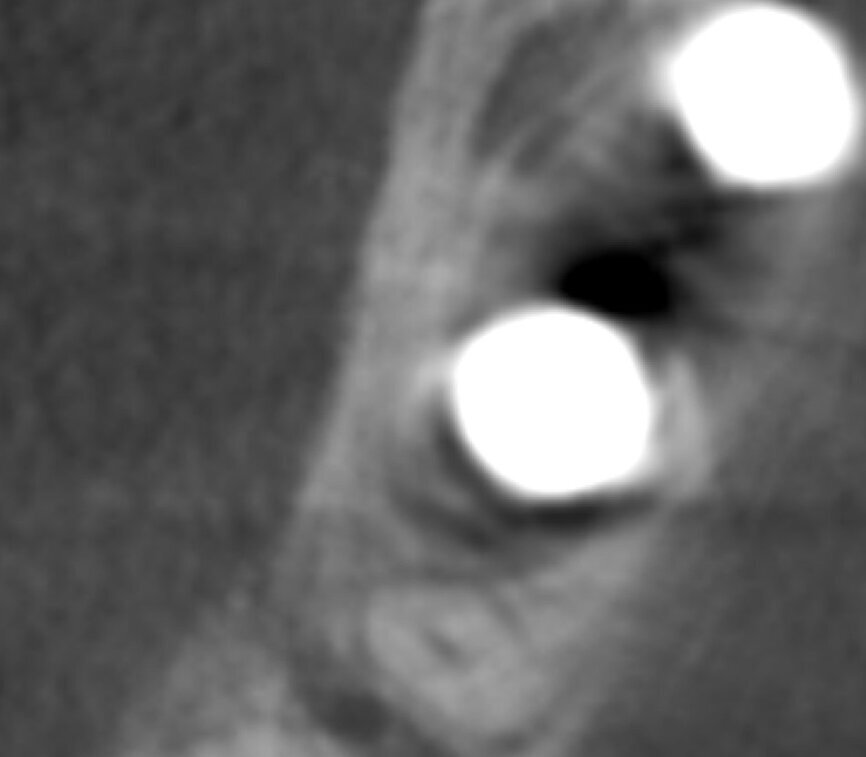

Fig.12a: The two-year follow-up post-op CBCT scan.

The two-year follow-up postoperative cone beam computed tomography (CBCT) scan (Figs. 11 & 12), as well as the clinical photographs, illustrated the bone level, the buccal bone volume achieved and maintained over the period. Also, it was possible to see that the gap distance, radiographically, appeared to have been filled with bone. It was surprising also to see that bone level was well above the implant–abutment junction, maybe in response to a very efficient maintenance of a zero micro-gap at the junction owing to this BioBlock (BTI Biotechnology Institute) one abutment, one time concept, providing a virtual one-piece implant.